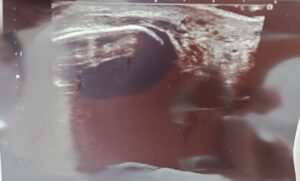

かなり腫れていて荷重不可能、エコーを撮ってみたら腓骨下端に裂離骨片が写りました😱

(剥離骨折という言い方は医学的には間違いです。)